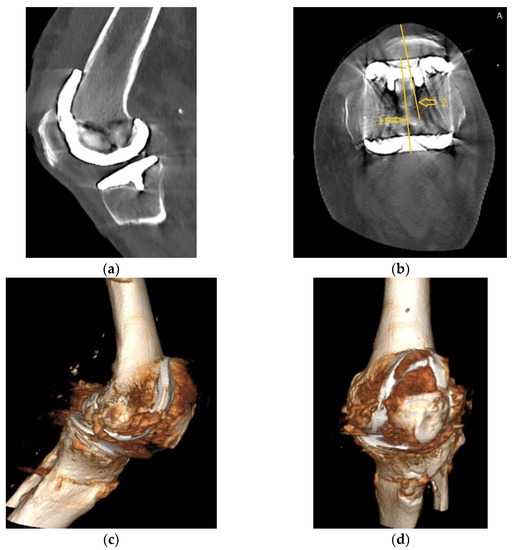

Four years ago, the patient was diagnosed with Ahlback stage IV gonarthrosis and underwent a simultaneous bilateral TKA surgery in another orthopedic clinic. Two NexGen cemented total prostheses were then implanted, with patellar resurfacing performed only on the right side, due to anesthetic complications which required a drastic shortening of the operating time, thus preventing the surgical team from performing resurfacing on the contralateral patella. Although postoperative radiological images showed a slight implantation error in the femoral component on the right side, extensive anterior resection with posterior rotation of the femoral component, the clinical outcome was satisfactory (Figure 1).

Figure 1.

Right knee, initial after surgery radiological image: (a) lateral view, extensive anterior resection, femoral posterior rotation, femoral component axis intersecting diaphyseal axis at a 15.4° angle with (1) marking the femoral diaphyseal axis and (2) marking femoral component rotation axis; (b) coronal view.